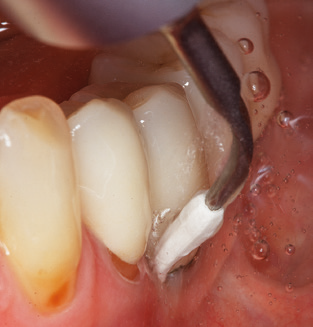

Good illumination of the working field facilitates the process considerably. The system used by the authors achieves this thanks to a 5x LED ring integrated in the handpiece. Naturally, a range of working tips for different indications is also offered. A straight, universally employable tip is the basic instrument required for machine cleaning of natural teeth (Fig. 5a and b). Curved tips, which allow access to exposed furcations, are also available for hard-to-reach areas in the posterior region (Fig. 6).